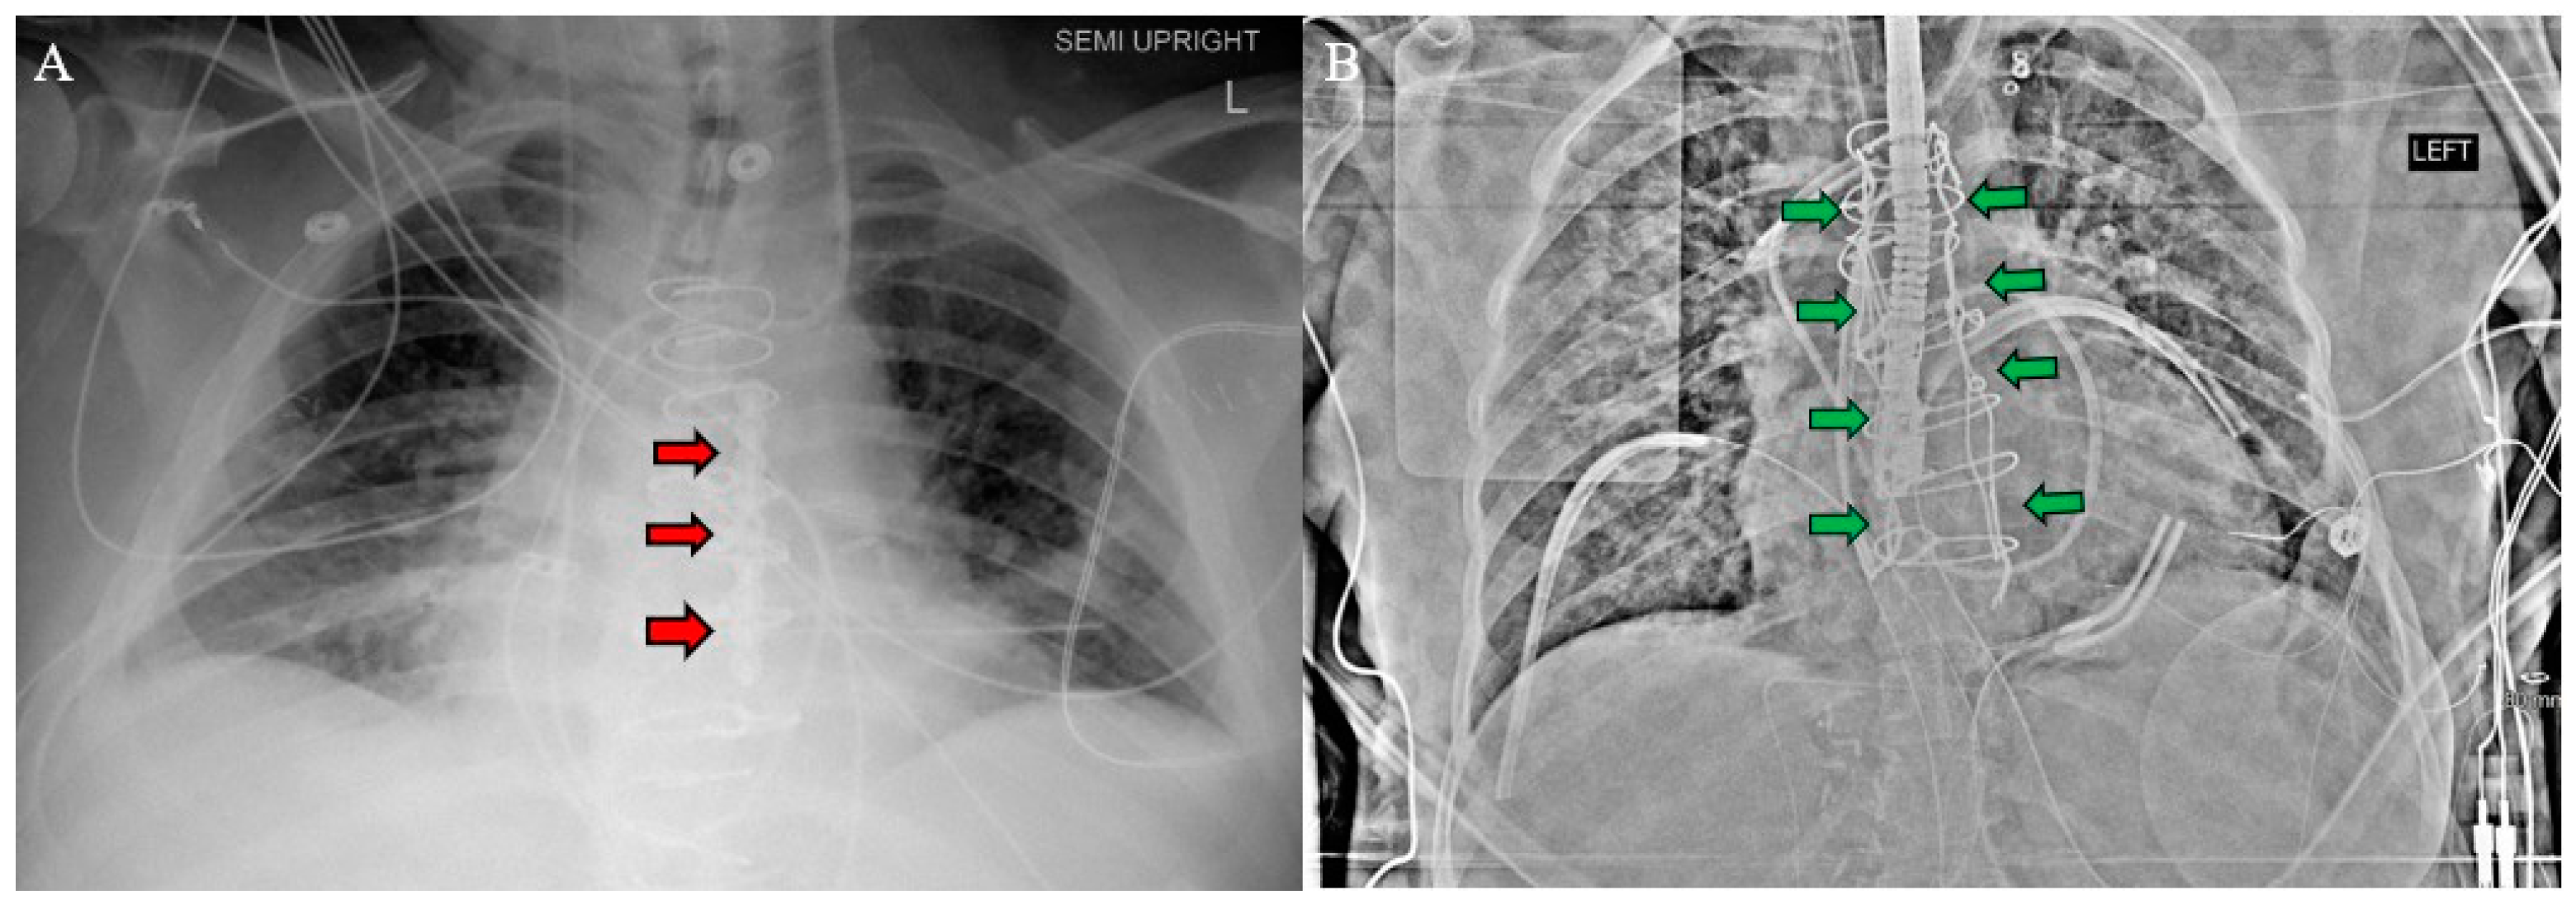

Figure 3. Postoperative chest X-ray for (A) Patient 1 and (B) Patient 2 demonstrate sternal plate used in Patient 1 (red arrows A) and Robicsek technique used in Patient 2 (green arrows B).

After establishing cardiopulmonary bypass through the inferior partial sternotomy, the two-stage sternotomy was then completed with the separation of the superior sternum with the oscillating saw. Direct SVC cannulation was established, and the remainder of the heart and great vessels were dissected. Severe, densely calcified adhesions were encountered between the aorta and the pulmonary artery, which required extensive dissection. Following this complex dissection, cardiectomy and transplant were performed routinely. After transplantation, the chest was left open and packed for hemostasis, and the patient was returned to the OR on POD 1 for sternotomy closure. One longitudinal sternal plate was used with sternal wires posterior to the plate to close the sternum (Figure 3A).

The postoperative course was complicated by prolonged inotrope requirement with difficulty weaning off dobutamine, substernal hematoma requiring drainage, and left internal jugular vein occlusive DVT requiring mechanical thrombectomy. These complications were all expected given the patient’s medical condition and unrelated to the two-stage sternotomy. Successful function of the transplanted heart was demonstrated with normal cardiac output on RHC, LVEF of 55–60% on TTE, and absence of evidence of acute rejection on endomyocardial biopsy (EMB). The patient was discharged 31 days post-transplant. As of six months post-transplant, the patient remained clinically stable and demonstrated excellent graft function and no evidence of rejection.

The patient’s history of repeated sternotomies again created a challenging reentry to the thorax. The preoperative CT revealed extensive adhesions between the right atrium and the inferior retrosternal surface with no pericardium present (Figure 4). Due to multiple previous interventions, the patient did not possess adequate peripheral vessels amenable to cannulation. The two-stage sternotomy approach was again utilized to address these adhesions. A partial sternotomy was initiated at the sternal notch and proceeded inferiorly to the third intercostal space, where an inverted T incision was made (Figure 2B). After the partial sternotomy, the aorta and SVC were carefully dissected and directly cannulated, and CPB was initiated. After CPB was initiated, the stepwise sternotomy was completed with the separation of the remaining inferior portion of the sternum. Due to the dense adhesions between the inferior sternum and the right atrium, the atrium was penetrated by the bone saw and the atrial cavity was directly exposed on opening of the chest. Fortunately, the CPB made for a bloodless field, and direct repair of the right atrial wall with a running Prolene suture was easily achieved. The remainder of the heart was dissected, with cardiectomy and transplantation performed according to standard procedure. The sternotomy was left open until the patient underwent OLT on POD1.

Prior to OLT on POD1, the CVP was mildly elevated, so continuous renal replacement therapy was initiated to remove fluid. The CVP came down appropriately, and OLT was performed without complication. The chest and abdomen were both simultaneously closed after liver transplantation, with a Robiscek technique utilized for sternal closure (Figure 3B). The patient recovered in the CTICU until POD17 as she required a prolonged course of dobutamine inotropic support, which was anticipated. The postoperative evaluation revealed a significant improvement in LVEF, tricuspid regurgitation, and cardiac output with no evidence of rejection on EMB. The patient remained in the CTICU until transfer to the general transplant medicine floor on POD17 and was discharged on POD58. As of three months post-transplant, the patient remained clinically stable with excellent graft function and no evidence of rejection.